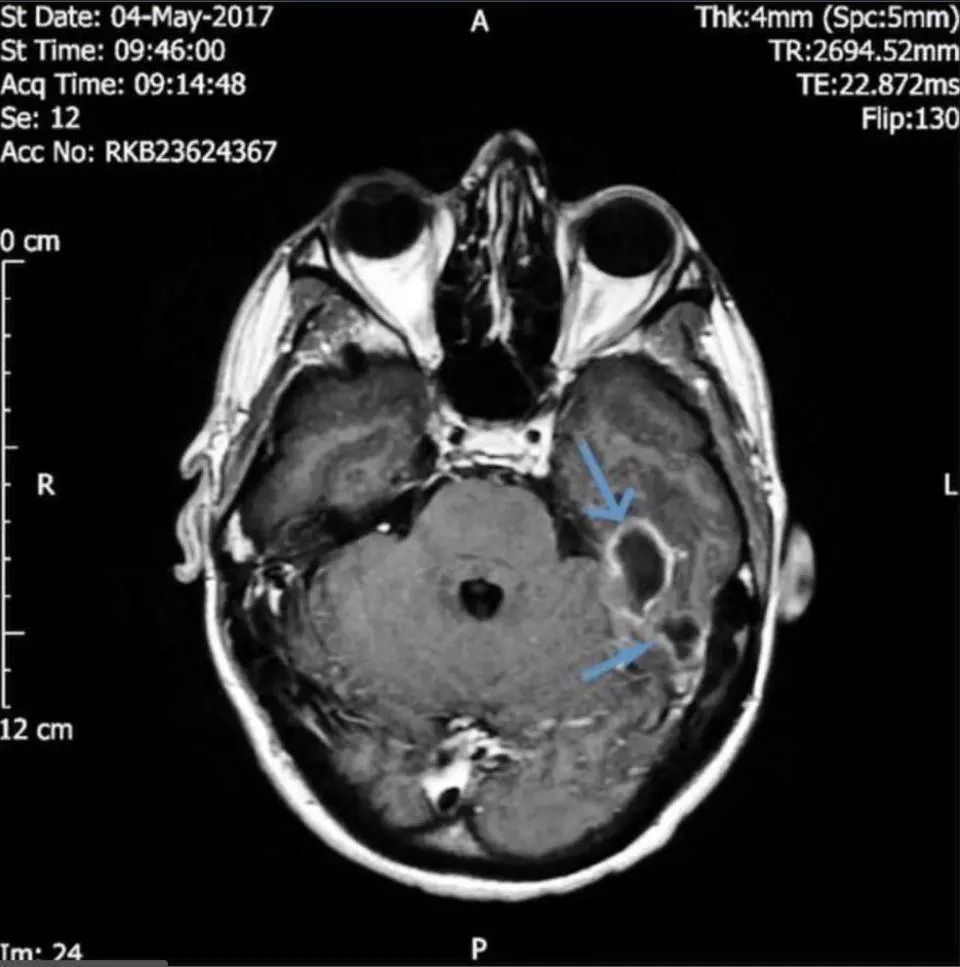

随着时间推移,感染已蔓延至大脑,从而引发了癫痫。医学团队的CT扫描显示:他的头骨下靠近左耳道的位置有两块充满脓液的肿块,再晚治疗情况就危险了。

为有效消除感染,医生进一步寻找着致病的根源。终于在脑成像的帮助下他们发现男子的耳道中有一个异物。经过鉴定,导致严重感染的东西是一小撮棉花。